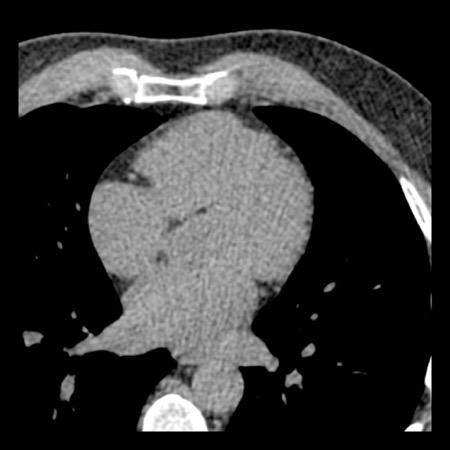

case 4 – CAD-RADS 3/P1/I+ thrombus left ventricle

First, scroll through the CTA images.

How would you describe the findings on the coronary CTA?

The findings are:

- Moderate (50-69%)

stenosis in the proximal LAD caused by a non-calcified plaque. - Variant of

sinoatrial (SA) nodal artery. The artery usually arises from the RCA as a second

branch after the conus artery, however in this case it arises from the LCX,

courses behind the aorta, anastomosing with the right atrium and with a small

branch supplies the SA-node of the heart. - Thrombus in the

apex of the left ventricle. - CTP was performed

in this patient. CTP showed a perfusion defect at stress imaging in the

territory of the LAD (I+), at rest no perfusion defect was visible.

This patient classifies as CAD-RADS 3/P1/I+, which means

this patient requires further investigation.